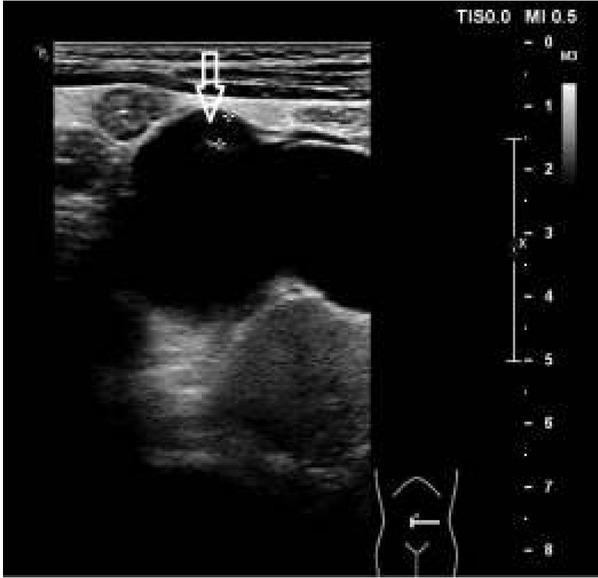

Ryc. 1